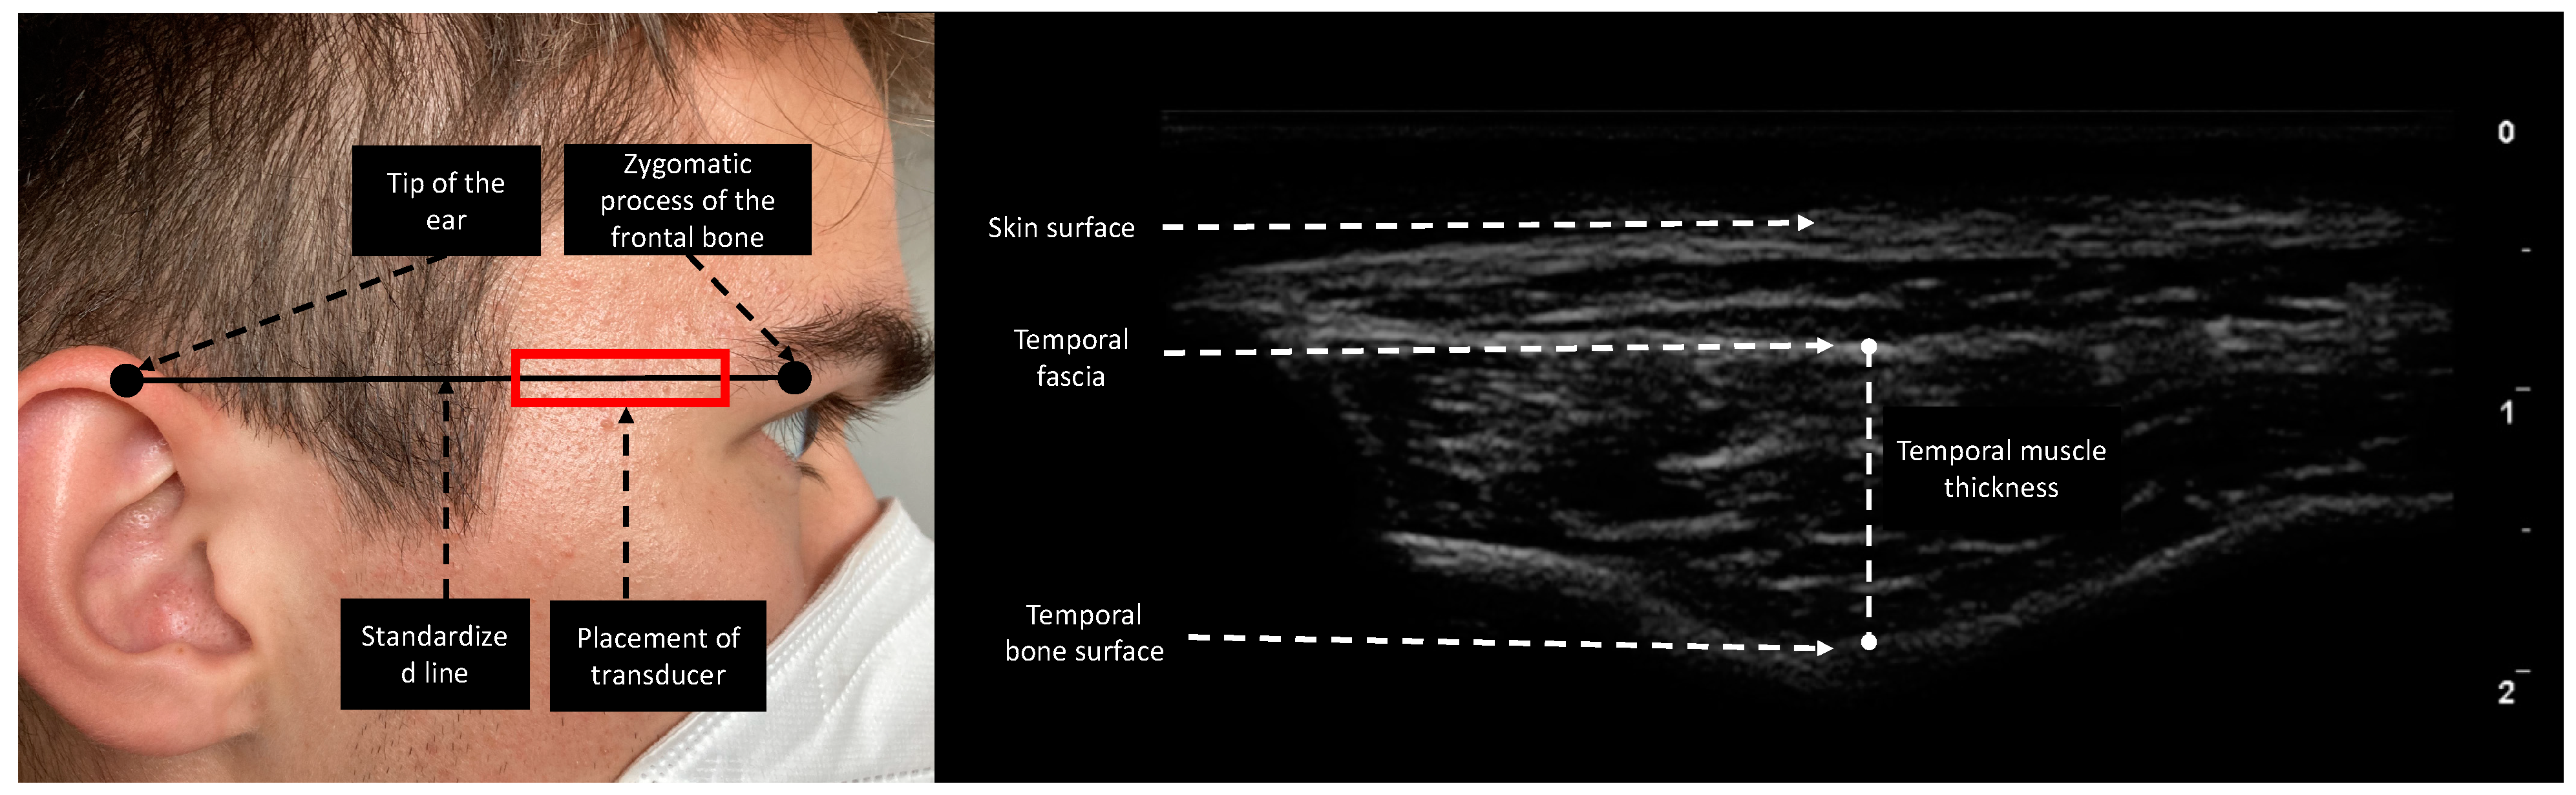

Esaote MyLabOmega with a 20 MHz linear probe was used to obtain images. Image acquisition of subcutaneous adipose tissue (SAT), rectus femoris thickness (RFT), rectus femoris cross-sectional area (RF CSA), and vastus intermedius thickness (VIT) was performed following the protocol provided by Galindo et al. on both lower extremities [16]. As suggested by Pardo et al., the probe was placed in the lower third of the connecting line between the anterior superior iliac spine and the upper border of the patella [17]. To ensure the same measurement location over the length of stay, we drew a line on the patient’s leg for probe placing. Device settings were kept identical for every patient and throughout the study period. In contrast to Chang et al., who moved the transducer cranially and parallel to the zygomatic arch until the temporal muscle was visible, we performed TMT measurements by placing the transducer on a fictive line between the zygomatic process of the frontal bone and the ipsilateral helix of the auricle (Figure 1), since this point can be identified more clearly in follow-up ultrasound acquisition processes and is furthermore comparable to the measurement point of TMT in CT [18,19]. TMT was defined as the distance between the temporal fascia and the lowest point of the temporal fossa (Figure 1). The transducer was placed rectangular to the skin with minimal pressure and bilateral measurements were performed if applicable. To reduce measurement interference, we instructed patients not to clench if not under sedation. To determine interrater reliability in ultrasound-based measurements, 20 patients were measured in parallel by two experienced examiners. The two observers were unaware of each other’s results and performed measurements independently.

Figure 1.

Measurement site of the temporal region. The reference line is the horizontal line connecting the zygomatic process of the frontal bone and the upper edge of the auricula. The transducer was placed rectangular to the skin. TMT was evaluated as the maximal distance between the temporal fascia and temporal bone surface.